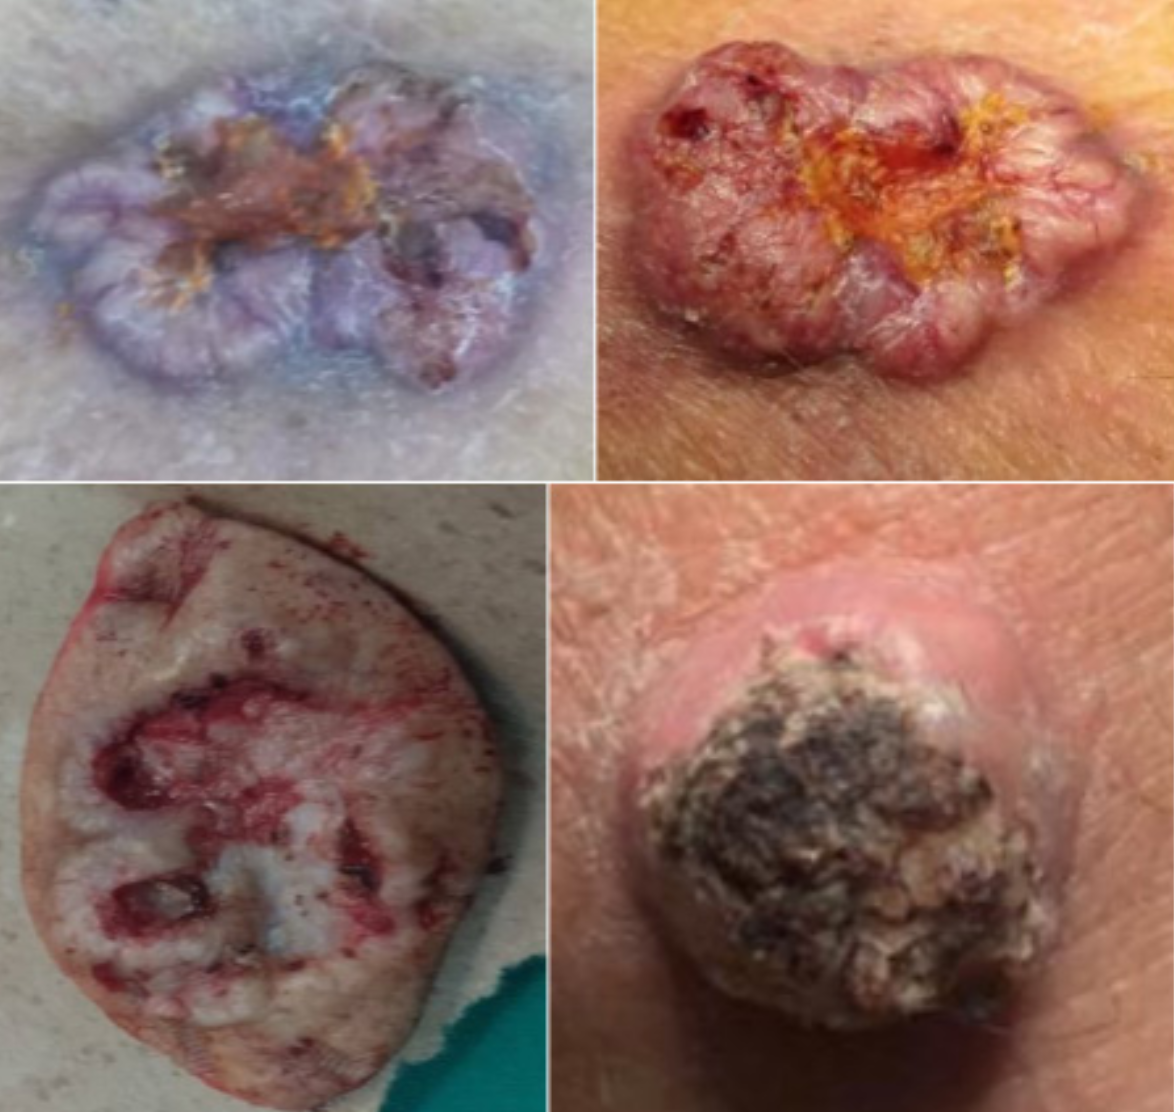

Diego Soto V, Melissa Pavez K, Sebastián Morales Z.

|

|